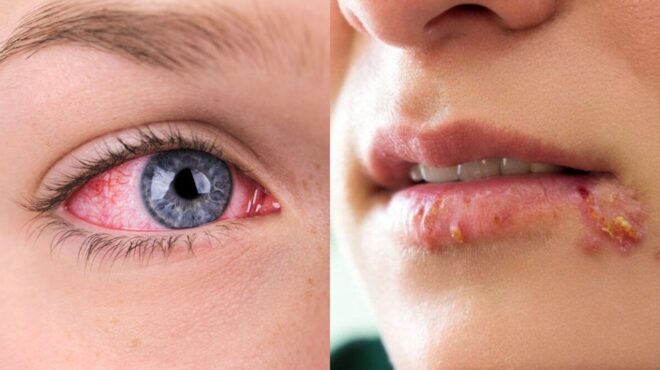

Προβλήματα στα πόδια: Φαγούρα

Η φαγούρα στα πόδια μπορεί να οφείλεται στο «πόδι του αθλητή», μία μυκητιασική μόλυνση που είναι πολύ συχνή κυρίως στους άνδρες ηλικίας 20-40 ετών. Επίσης μπορεί να οφείλεται σε δερματίτιδα, δηλαδή σε αντίδραση σε κάποιο χημικό ή προϊόν περιποίησης, και να συνοδεύεται από κοκκινίλα ή εμφάνιση ξηρών περιοχών. Εάν το δέρμα στην περιοχή που έχετε φαγούρα, είναι παχύ και μοιάζει να έχει εξανθήματα ίσως πρόκειται για ψωρίαση που οφείλεται σε υπεραντίδραση του ανοσοποιητικού συστήματος. Επιπλέον διαβάστε